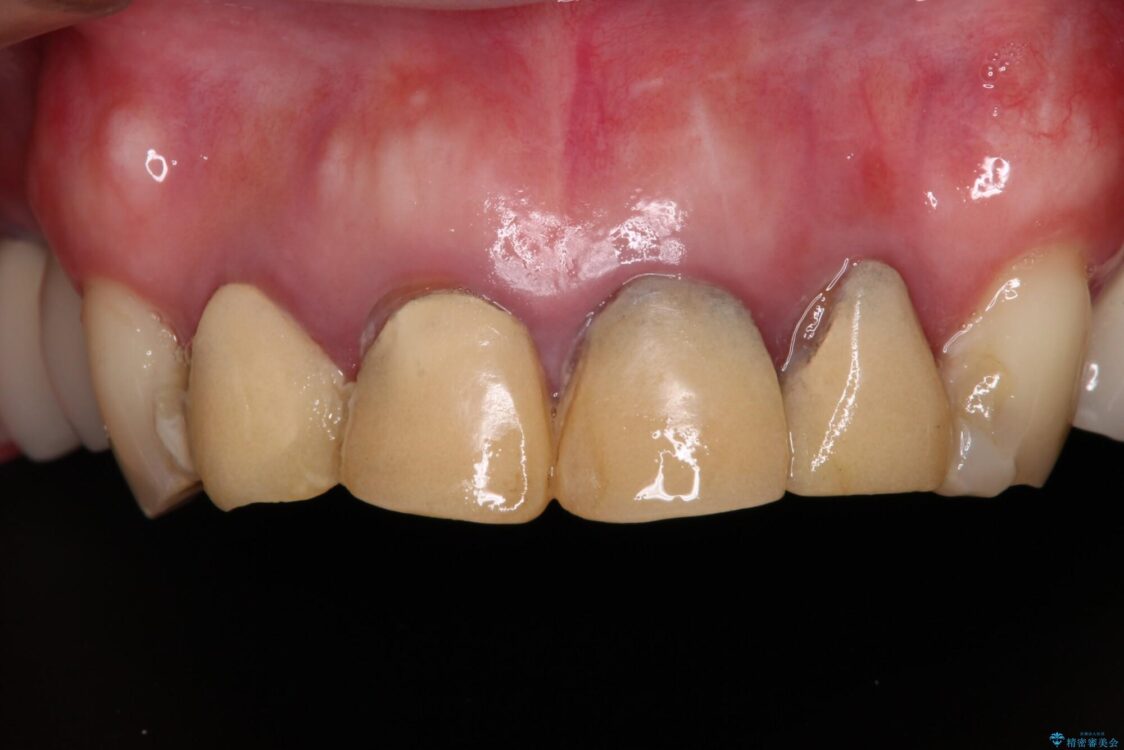

仮歯が不適合で歯肉が腫脹していたため、しっかりと調整した新しい仮歯にして腫れを改善した上で、オールセラミッククラウンにて補綴することとしました。

日頃の歯磨きをしっかりと行ってくださるので、新しい仮歯に変えてから速やかに歯肉の状態が改善されました。

治療前

• 仮歯のまま放置した前歯 オールセラミッククラウンで自然な前歯に 治療前画像